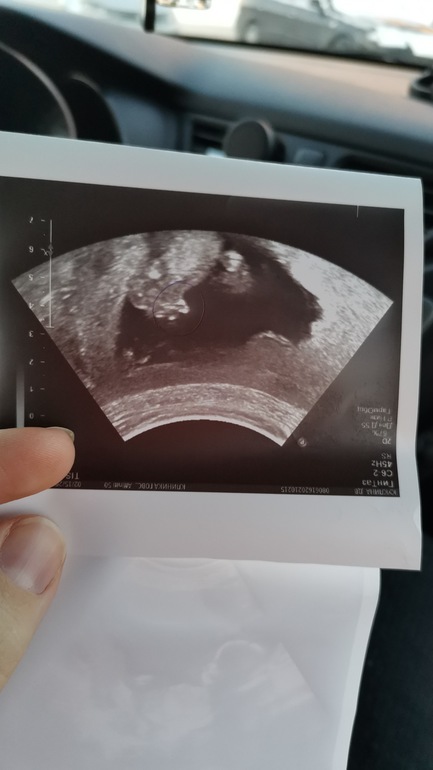

Узи. Опережение по срокам.15 или 17??недель..+ сказали пол(фото)

УЗИ, КТГ, доплерСходила сегодня на Узи.. Срок по мес 15.2... Срок по Узи 16.6

Обхват живота вообще 17.6 недель.. Это нормально? У кого нибудь так было??

Меняэто пугает.. Но врач узи сказала ничего страшного не видит внутренние органы в норме.

БПР 33.8(16.4)

ОГ 133.1(16.1)

ОЖ 119.3 ( 17.5)

ДБ 17.4 (15.2)

Вес 158 гр

Еще нам скащали предподожительно пол... Будет мальчик.. Дали фото..